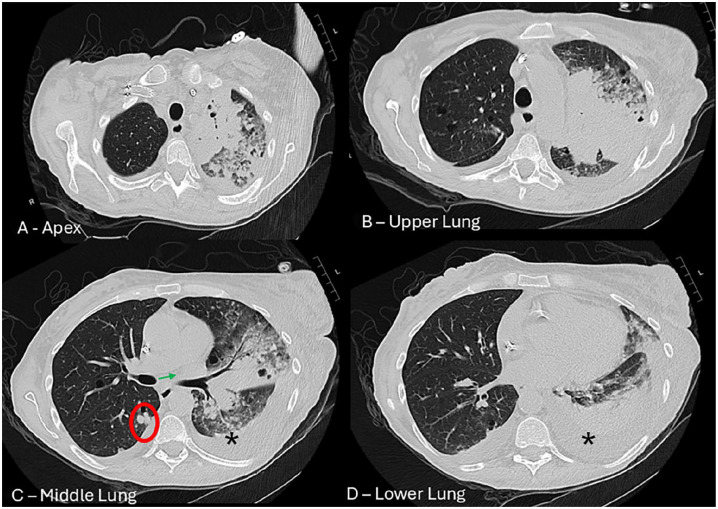

Blastomycosis is a systemic fungal infection caused by Blastomyces dermatitidis, primarily found in the Ohio and Mississippi River valleys. It often presents nonspecific symptoms, and while pulmonary involvement is common, progression to acute respiratory distress syndrome (ARDS) is rare but severe. This report examines a 55-year-old female patient with multiple comorbidities who developed ARDS due to blastomycosis. Imaging revealed multilobar infiltrates and pleural effusion, with cultures confirming blastomycosis. Despite broad-spectrum antibiotics and antifungal therapy, a delayed diagnosis led to respiratory failure and death. The case emphasizes the diagnostic challenges of blastomycosis, which can mimic conditions like bacterial pneumonia and malignancy. Treatment with amphotericin B is crucial for severe cases, but delays in diagnosis can worsen outcomes. This highlights the necessity for prompt diagnosis and comprehensive management, including early recognition of fungal infections in critically ill patients.